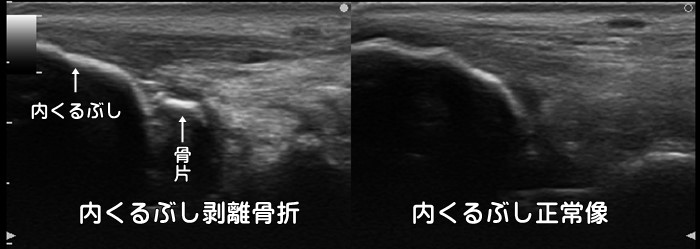

脛骨・腓骨剥離骨折

足首を捻挫した際に、靭帯に牽引されて内くるぶしや外くるぶしの先端が剥離骨折する事があります。ある統計では10歳以下:77% 11~14歳:19% 15~18歳:13%で剥離骨折が発症すると言われています。一般に子供の場合、靭帯よりも骨の方が弱い為、捻挫をすると靭帯断裂よりも剥離骨折が多く発症します。炎症反応の動画はこちらで確認できます。